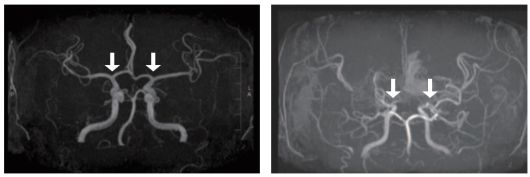

일반인의 뇌혈관(왼쪽)과 모야모야병 환자 뇌혈관(오른쪽). 자료 서울대병원 |

모야모야병은 뇌로 혈액을 공급하는 혈관이 이유 없이 점차 좁아지는 병이다. 주로 10세 전후 소아와 40세 전후 성인에서 발병하며, 뇌혈관이 막히거나 파열되는 문제가 발생하곤 한다. 특히 어린 환자는 허혈성 뇌졸중(뇌경색)이 빈번하게 나타난다. 하지만 국내 소아 환자 특성을 체계적으로 분석한 자료는 거의 없었다.